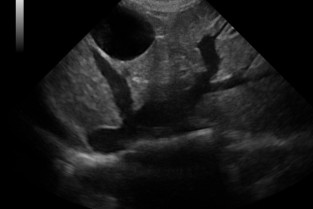

Ces travaux pratiques, réalisés par manipulation sur les chiens de compagnie appartenant aux participants, s’adressent à des vétérinaires canins désirant se former à l’échographie et disposant d’un échographe dans leur pratique quotidienne, ou souhaitant en acquérir un rapidement.

- d’identifier tous les organes lors d‘une échographie abdominale ;

- il sera également capable de reconnaitre un aspect normal échographique pour chaque organe ;